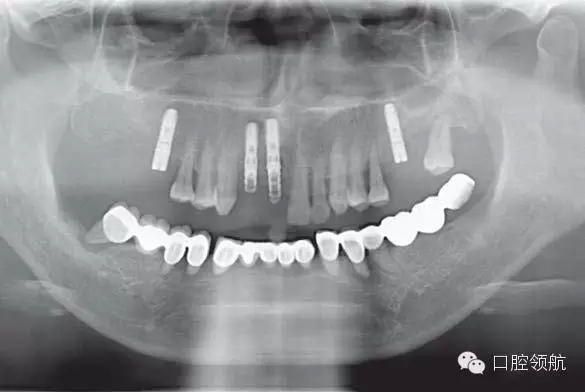

圖6-16為過渡義齒佩戴后的全景片。這張全景片的作用是確認螺絲固位過渡義齒的臨時內(nèi)冠復合基臺與復合基臺完全就位。如果全景片無法準確確認時,建議拍攝小牙片確認所有的臨時內(nèi)冠復合基臺就位完好。過渡義齒就位不良,是引起All-on-4種植體早期脫落的一個主要原因。確認就位后開始咬合調(diào)整。

10.webp.jpg

圖6-16 下頜All-on-4過渡義齒戴牙后的全景片